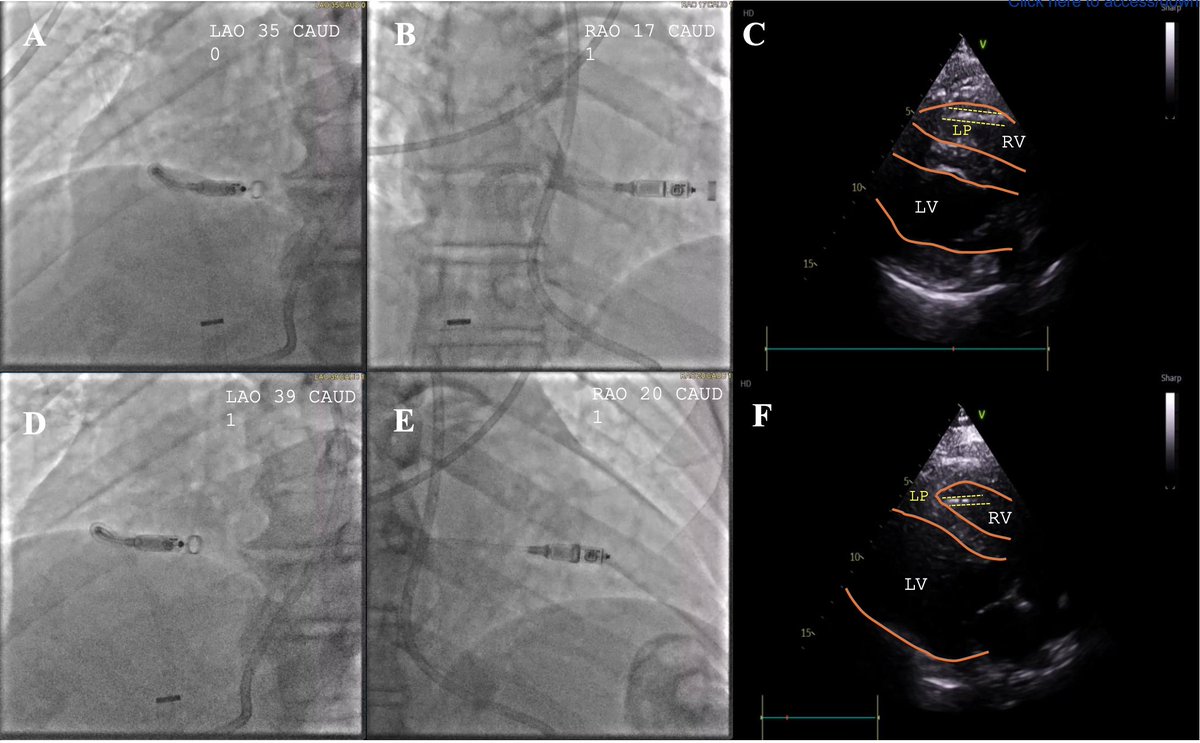

**Study 3: Step-by-step approach to ultrasound-guided leadless pacemaker implantation @DJ_Lakkireddy @MohitTuragam @jkewcharoen et al share a practical, image-guided protocol using TTE, ICE, or TEE to optimize LP placement and reduce contrast/radiation exposure. *Echo confirms